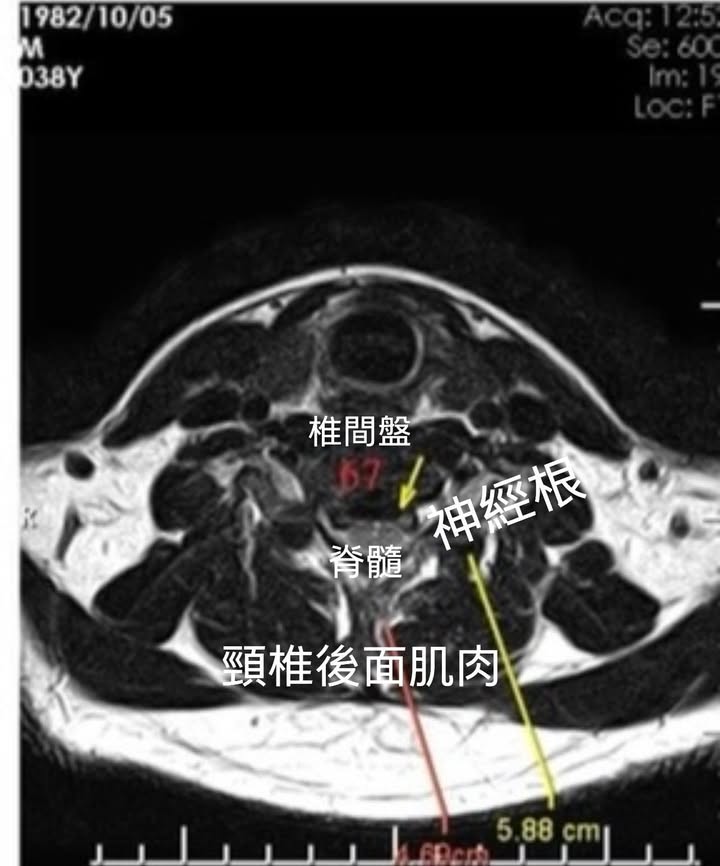

2.C6C7神經根型頸椎病->雙側壓迫,右側最嚴重

椎間盤突出,相鄰椎體後緣及外側緣的骨刺形成,小關節及鉤椎關節的增生肥大,黃韌帶的增厚及向椎管內形成皺摺。都可能刺激或壓迫椎管兩旁的頸神經根,引起上肢包括手指的疼痛、麻木和肌力減退等症狀。